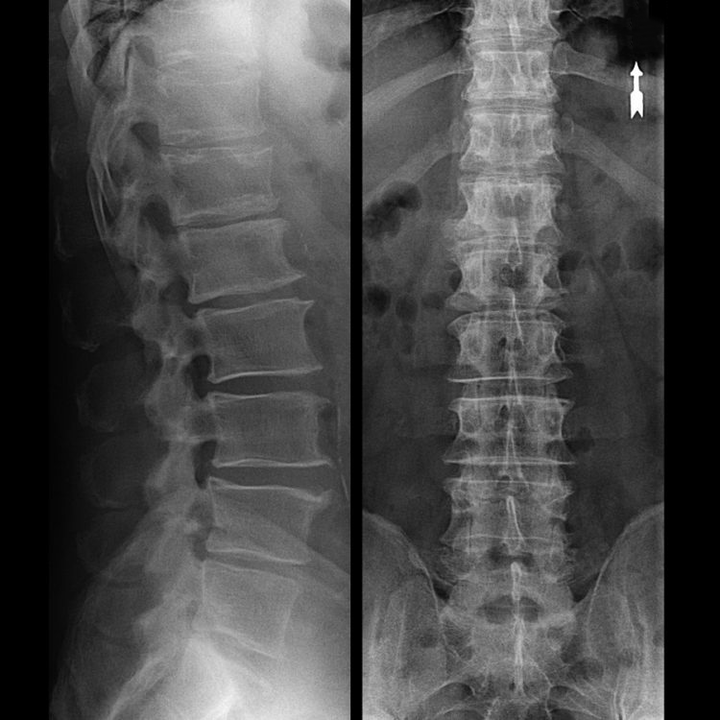

In typical cases, osteochondrosis of the cervical and cervicothoracic spine occurs as described above.Therefore, the main stage of diagnosis was and remains the identification of the patient's complaints, establishing the presence of concomitant muscle spasm by simple palpation of the muscles along the spine.Is it possible to confirm the diagnosis of osteochondrosis by radiographic examination?

An “X-ray” of the cervical spine, and even with functional tests of flexion and extension, does not show cartilage, since its tissue transmitsFunctional testing can confirm the diagnosis of cervical spine instability.

Since the discs themselves can only be seen by CT or MRI, magnetic resonance imaging and X-ray computed tomography are indicated to clarify the internal structure of the cartilage and formations such as protrusions and hernias.Therefore, with the help of these methods, an accurate diagnosis is made, and the result of tomography constitutes an indication, and even a topical guide, for surgical treatment of hernia in the neurosurgery department.

- You can regularly do at least an x-ray of the lumbar spine in two projections, or an MRI, to find out if the hernia, if present, is progressing;